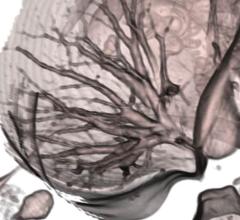

Videos | Cardiac Imaging

ITN and DAIC Editor Dave Fornell highlights the latest advancements that will impact cardiovascular imaging from the…

Feature | Dave Fornell

The latest advances in cardiovascular imaging are usually shown first at the Radiological Society of North America (…